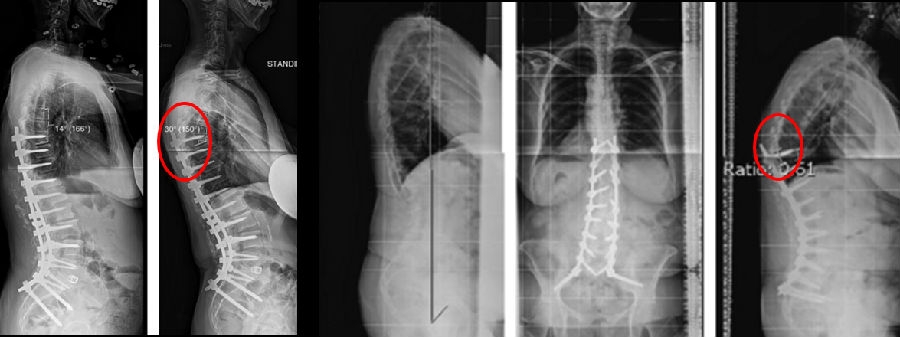

1) 矢状面失平衡(High SVA)过度矫正

术前-术后SVA矫正过大(大于5cm)的患者,PJK发生的风险增高

矫形术后矢状面失平衡可增加固定融合近端和远端交界区的应力,增加PJK风险

图16 矢状面失平衡过度矫正

SVA随着年龄增加,理想SVA矫正应综合考虑患者病情采用个性化矫形方案。

2)腰椎前凸(LL)过度矫正

图17 据文献报道,腰椎前凸(LL)过度矫正和SVA基线位置不当,均为增加PJK发生的风险因素